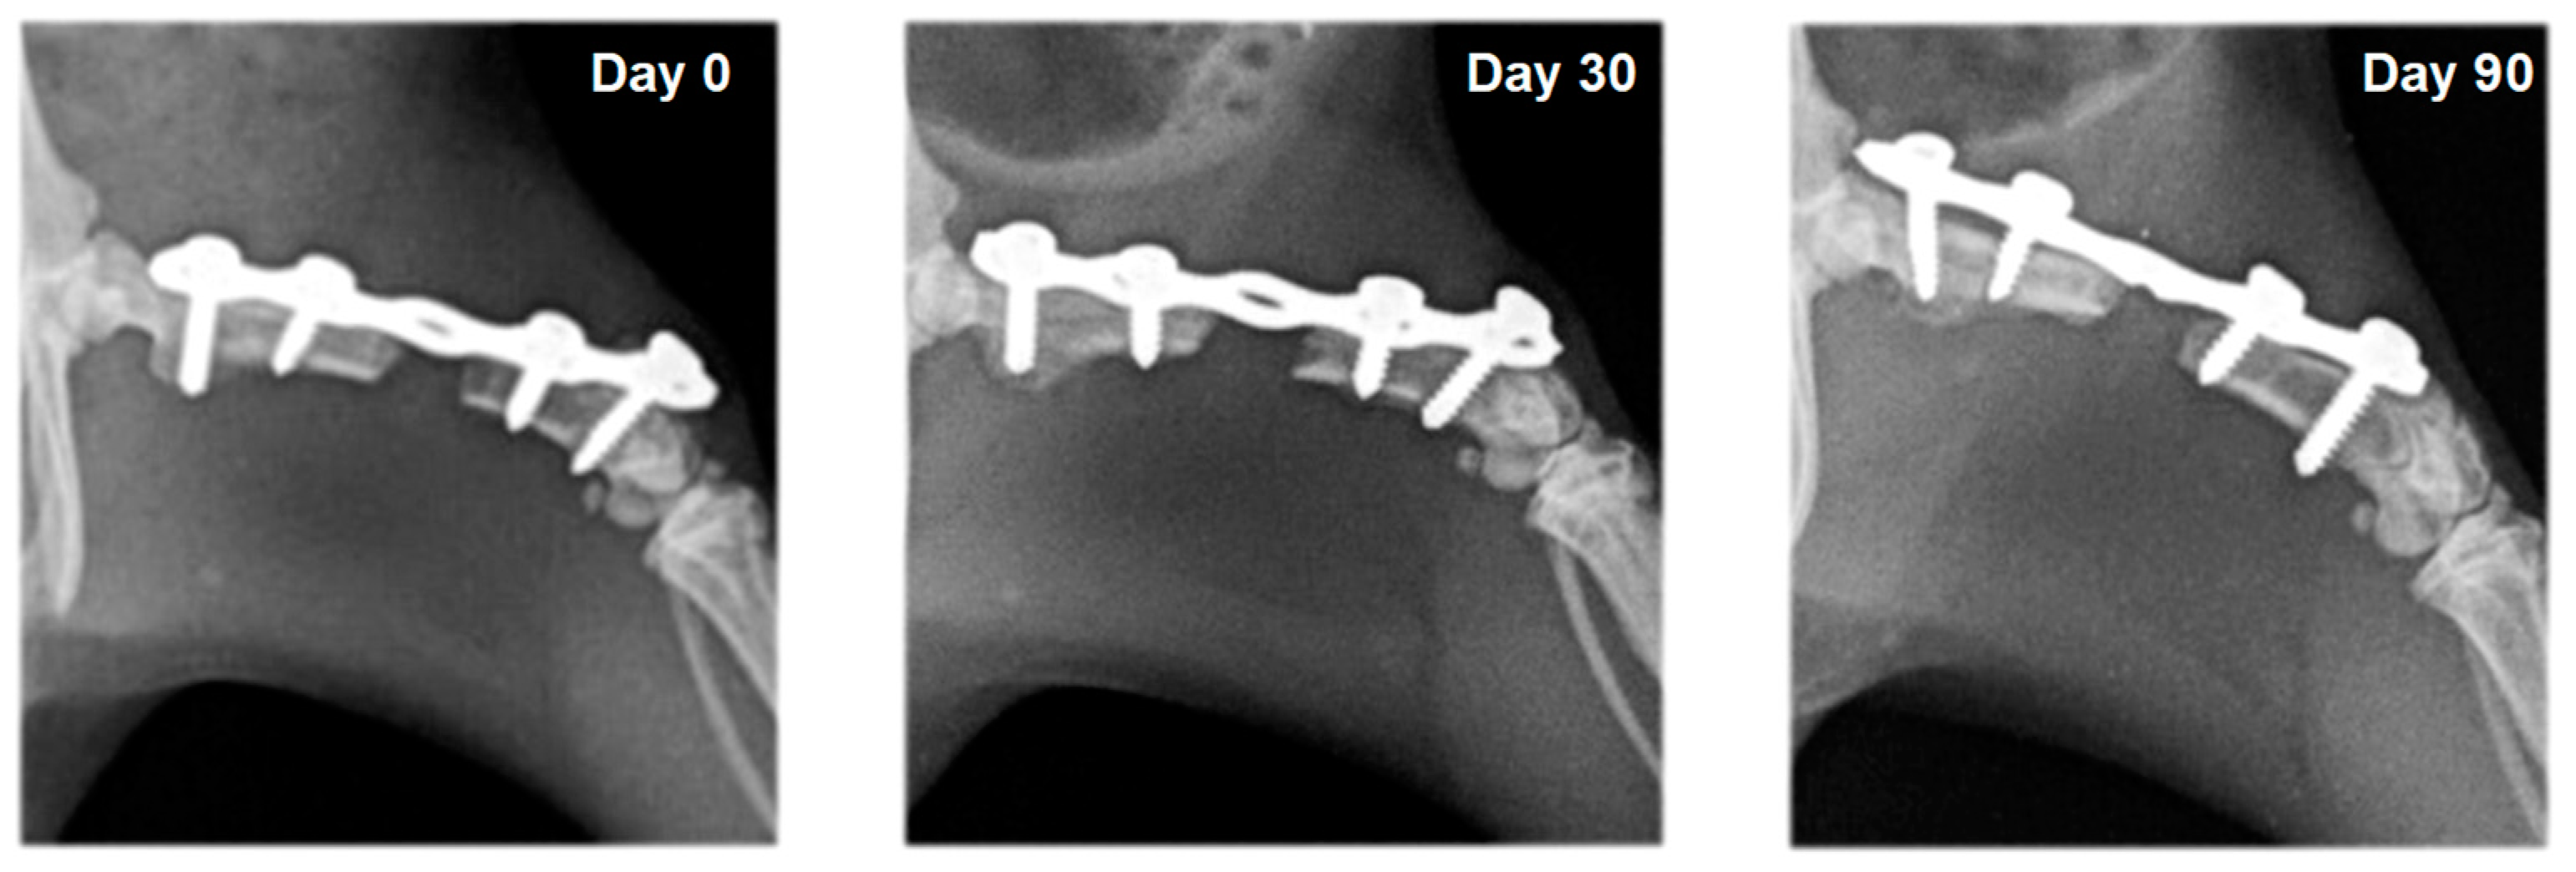

3.2. Radiography